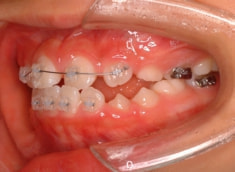

治療開始から約10ヶ月後